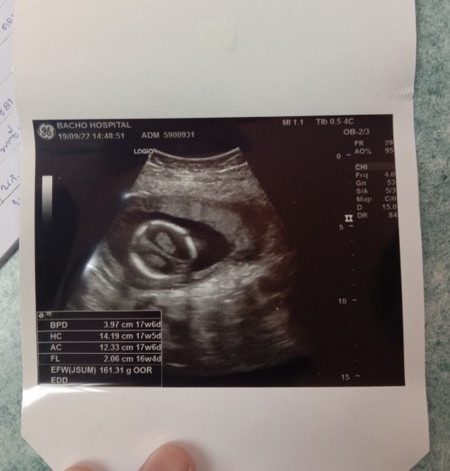

แบบนี้แฝดไหมค่ะ

สอบถามหน่อยค่ะ ใบอัลตราซาวด์แบบนี้แฝดไหมค่ะตอนซาวด์หมอไม่ได้บอกอะไรแต่พี่ๆแถวบ้านบอกว่าเหมือนได้แฝดเลยค่ะ